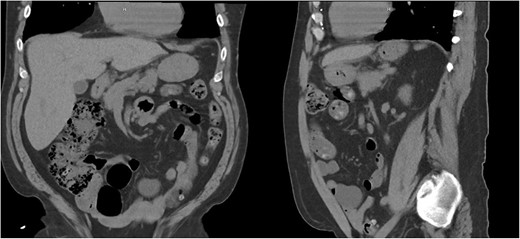

He was admitted for nasogastric decompression and underwent an upper endoscopy with benign findings. Once stable, he was discharged and optimized as an outpatient by adhering to a high-protein liquid diet. He underwent a scheduled robotic-assisted transabdominal preperitoneal (r-TAPP) repair of a type 4 anterior diaphragmatic hernia with mesh. The robot was docked and targeted with four 8 mm robotic ports across the mid-abdomen. A moderately sized hernia containing a loop of the transverse colon was identified. This was gently reduced (Fig. 3).

The falciform ligament was taken down with bipolar cautery. A peritoneal flap was created commencing about 4 cm inferior to the defect. A preperitoneal dissection was then performed to create the flap and to reduce the sac out of the mediastinum (Fig. 4).

Care was taken to avoid injury to the pleura and the pericardium. Once the sac was reduced, the defect’s size was measured as 9 cm in horizontal length by 4 cm in vertical dimension. Primary closure of the defect was performed with a running 0 V-loc absorbable 180 suture.